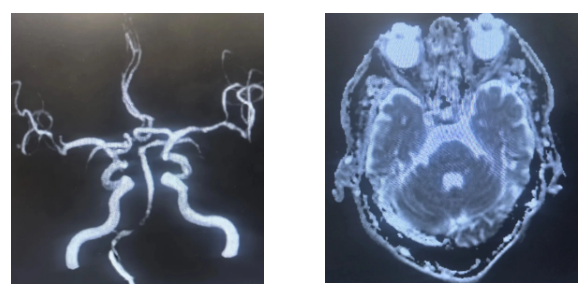

为明确诊断并制定治疗方案,神经内科与介入科医生团队迅速开展联合会诊,一致认为介入治疗是首选方案。随后,由独建库主任在DSA(数字减影血管造影)引导下,成功为患者实施了介入手术。

• 颈部血管超声:无创、便捷,可初步评估锁骨下动脉及椎动脉的血流情况。

• CTA或DSA(血管造影):可清晰显示血管狭窄的位置和程度,是诊断的金标准。